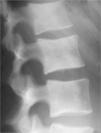

Osteomesopicnosis: aportación de tres casos

E. de la Hoz Adamea, B. Domínguez Fuentesa, D. García Gila, P. Moise Cosanob

a Servicio de Medicina Interna. Hospital Universitario de Puerto Real. Cádiz

b Servicio de Radiodiagnóstico. Hospital Universitario de Puerto Real. Cádiz